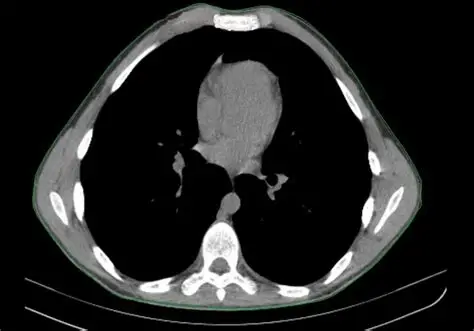

Диагноз подтверждают клинически и на визуализации (чаще КТ грудной клетки). Для объективной оценки применяют индекс Холлера (Haller Index), рассчитываемый по КТ: значения > 3.25 обычно указывают на выраженную деформацию, особенно если есть симптомы.

- Индекс Холлера и данные КТ/МРТ грудной клетки.

- КТ грудной клетки на диске/в портале (для расчёта индекса Холлера).